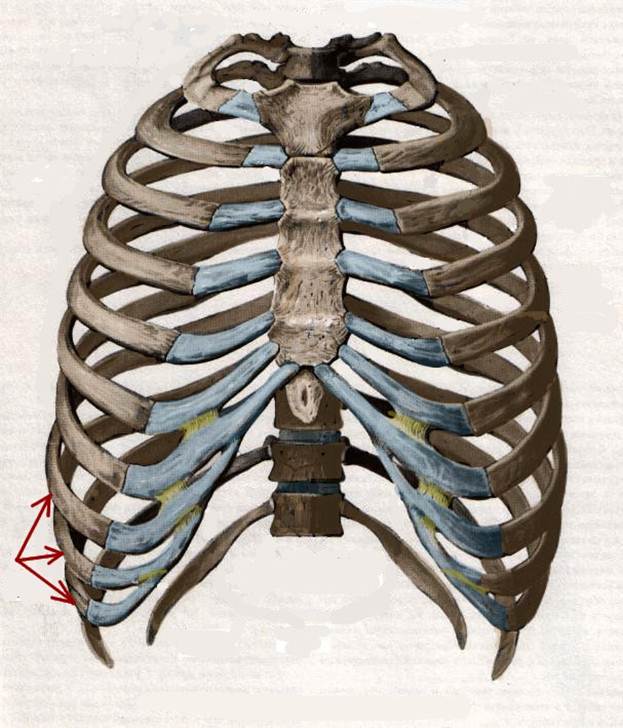

S: Стрелки указывают на сostae spuriae (латинский язык).